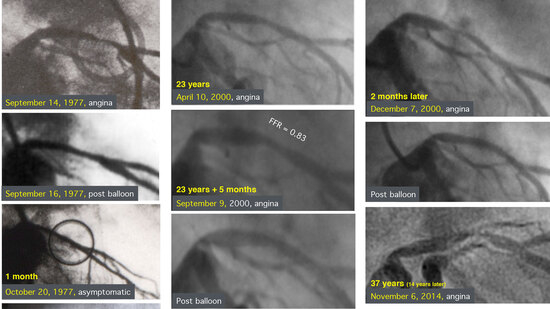

Being promoted to a staff position in cardiology in what appears to be the world’s speediest career of any cardiologist, i.e., virtually no training in cardiology, miniaturisation of this equipment and application to the coronary arteries became first priority. This required industrial machines and the Schneider company took over the balloon catheter production. The first coronary balloon for what was initially going to be called percutaneous transluminal coronary angioplasty (PTCA) and subsequently percutaneous coronary intervention (PCI) was not fed over a guide wire like the peripheral dilatation balloons. As fluoroscopy resolution was poor at that time and still frames or even replay were not a feature yet, Grüntzig needed distal pressure measurements for immediate assessment of the effect of PCI. Only the processed 35 mm cinefilm had adequate resolution to see the lumen and dissection flaps. However, it was highly unpractical to repeatedly stop the procedure for processing the cinefilm, which took about 20 minutes. In addition to the lumen for pressure measurement, a lumen for balloon filling was required and there was no room for feeding a wire through the shah on top of that. This balloon was not steerable, but other than that it could still be used nowadays, at least for a proximal PCI. While the balloon was tested in dogs and ready in early 1976 for a first human case, it was not until September 16, 1977 that PCI was finally performed in a patient for the first time worldwide. Even several trips to the United States (USA) to find a first patient had been futile. At the time, both in the USA and, much more, in Europe, indications for coronary angiography were very restrictive. Patients usually had to have experienced long periods of angina pectoris refractory to multiple drugs, which usually included a history of one or more myocardial infarctions, before they were considered for invasive work-up. Just about never did this then reveal singl-evessel disease, let alone a proximal discrete stenosis such as Grüntzig was looking for. Grüntzig was just returning from another trip to San Francisco, California, USA, again quite frustrated at not finding a suitable patient, when I presented him with a 38-year-old man (the same age as Grüntzig’s), who had been suffering from daily angina attacks for several weeks, was put on a bicycle ergometer (not quite what would be done today), and was found to have severe ST-segment elevation, ventricular tachycardia, and chest pain during exercise. An exception was made and he was subjected to coronary angiography revealing a single proximal stenosis of the left anterior descending coronary artery (LAD). Coronary artery bypass grahing (CABG) was scheduled, but I was the resident responsible for him and I had a better idea. Grüntzig was utterly pleased with the case and took me to the patient on the spot to obtain oral consent. Quite bluntly he told the patient that he was going to try something that had never been done in humans but worked in leg arteries and had also worked in dogs, and that there was a risk that immediate CABG would become necessary if it did not work out. The patient still recalls this conversation and how he immediately trusted Grüntzig and found nothing wrong with at least a reasonable chance to avoid open chest surgery. The procedure was performed the next day, as Grüntzig had obtained the necessary nods from the head of his department and the head of the Department of Cardiac Surgery long ago. The crowd attending was not really a crowd but rather a handful. Surgical stand-by (drop-by actually) was inaugurated with that case as two cardiac surgeons dropped in and out during the procedure. The patient tolerated the balloon inflation well and the lesion was remedied, yielding what would nowadays be called a stent-like result. The patient left the catheterisation laboratory with a transient right bundle branch block which recurred during a thallium exercise stress test two days later, which also revealed some, but improved, ST-segment elevation and reduced thallium uptake. It was thought at the time that this was a normal finding after PCI. I was never to see anything like that again and I doubt that Grüntzig was. The patient is still alive and well, now 76 years old. He had two additional episodes of chest pain, one 23 years after the procedure requiring first a bare metal stent (BMS) close to the initial lesion and a few months later a re-dilatation for in-stent restenosis, and one at 37 years requiring a drug-eluting stent (DES) again in the vicinity of the initial lesion plus one in the proximal part of the right coronary artery. Figure 1 shows the milestone angiograms of this historical patient. Exercise stress tests the day after this last procedure and 6 months later were normal and the patient still enjoys life without physical restrictions. While he had not taken any drugs for decades after his first procedure, he now accepted the idea of a lifelong single antiplatelet compound and a statin, in spite of his conviction that drugs taken chronically lost their effect.

Figure 1. PCI number 1 in the world (a man, 38-year-old at the initial and 75-year-old at the latest procedure). The pictures have to be read in chronological order first left top to bottom, then centre to bottom, and finally right top to bottom. The lesion shown on April 10, 2000 in an angiography indicated by angina would normally have been a perfect indication for PCI to me. In this particular case I preferred to refrain from angioplasty, not to spoil the so far perfect story, albeit the lesion was slightly more proximal than the original one. The patient kept his symptoms and insisted on having treatment. Thus the angiogram was repeated on September 9, 2000. To find an excuse again not to dilate, I performed the only clinical fractional flow reserve (FFR) measurement in my career and used the normal result to convince the patient that he needed no treatment. However, he insisted and got a reasonably good balloon angioplasty result which I would have accepted had he not insisted on a stent. It took only a few weeks for an in-stent restenosis to develop (drug-eluting stents [DESs] were not yet available) which had to be re-dilated. Another 14 years later a new lesion somewhere in-between this stent and the original site caused angina again and was stented, this time with a DES. At the same time the right coronary artery also received a DES (not shown).